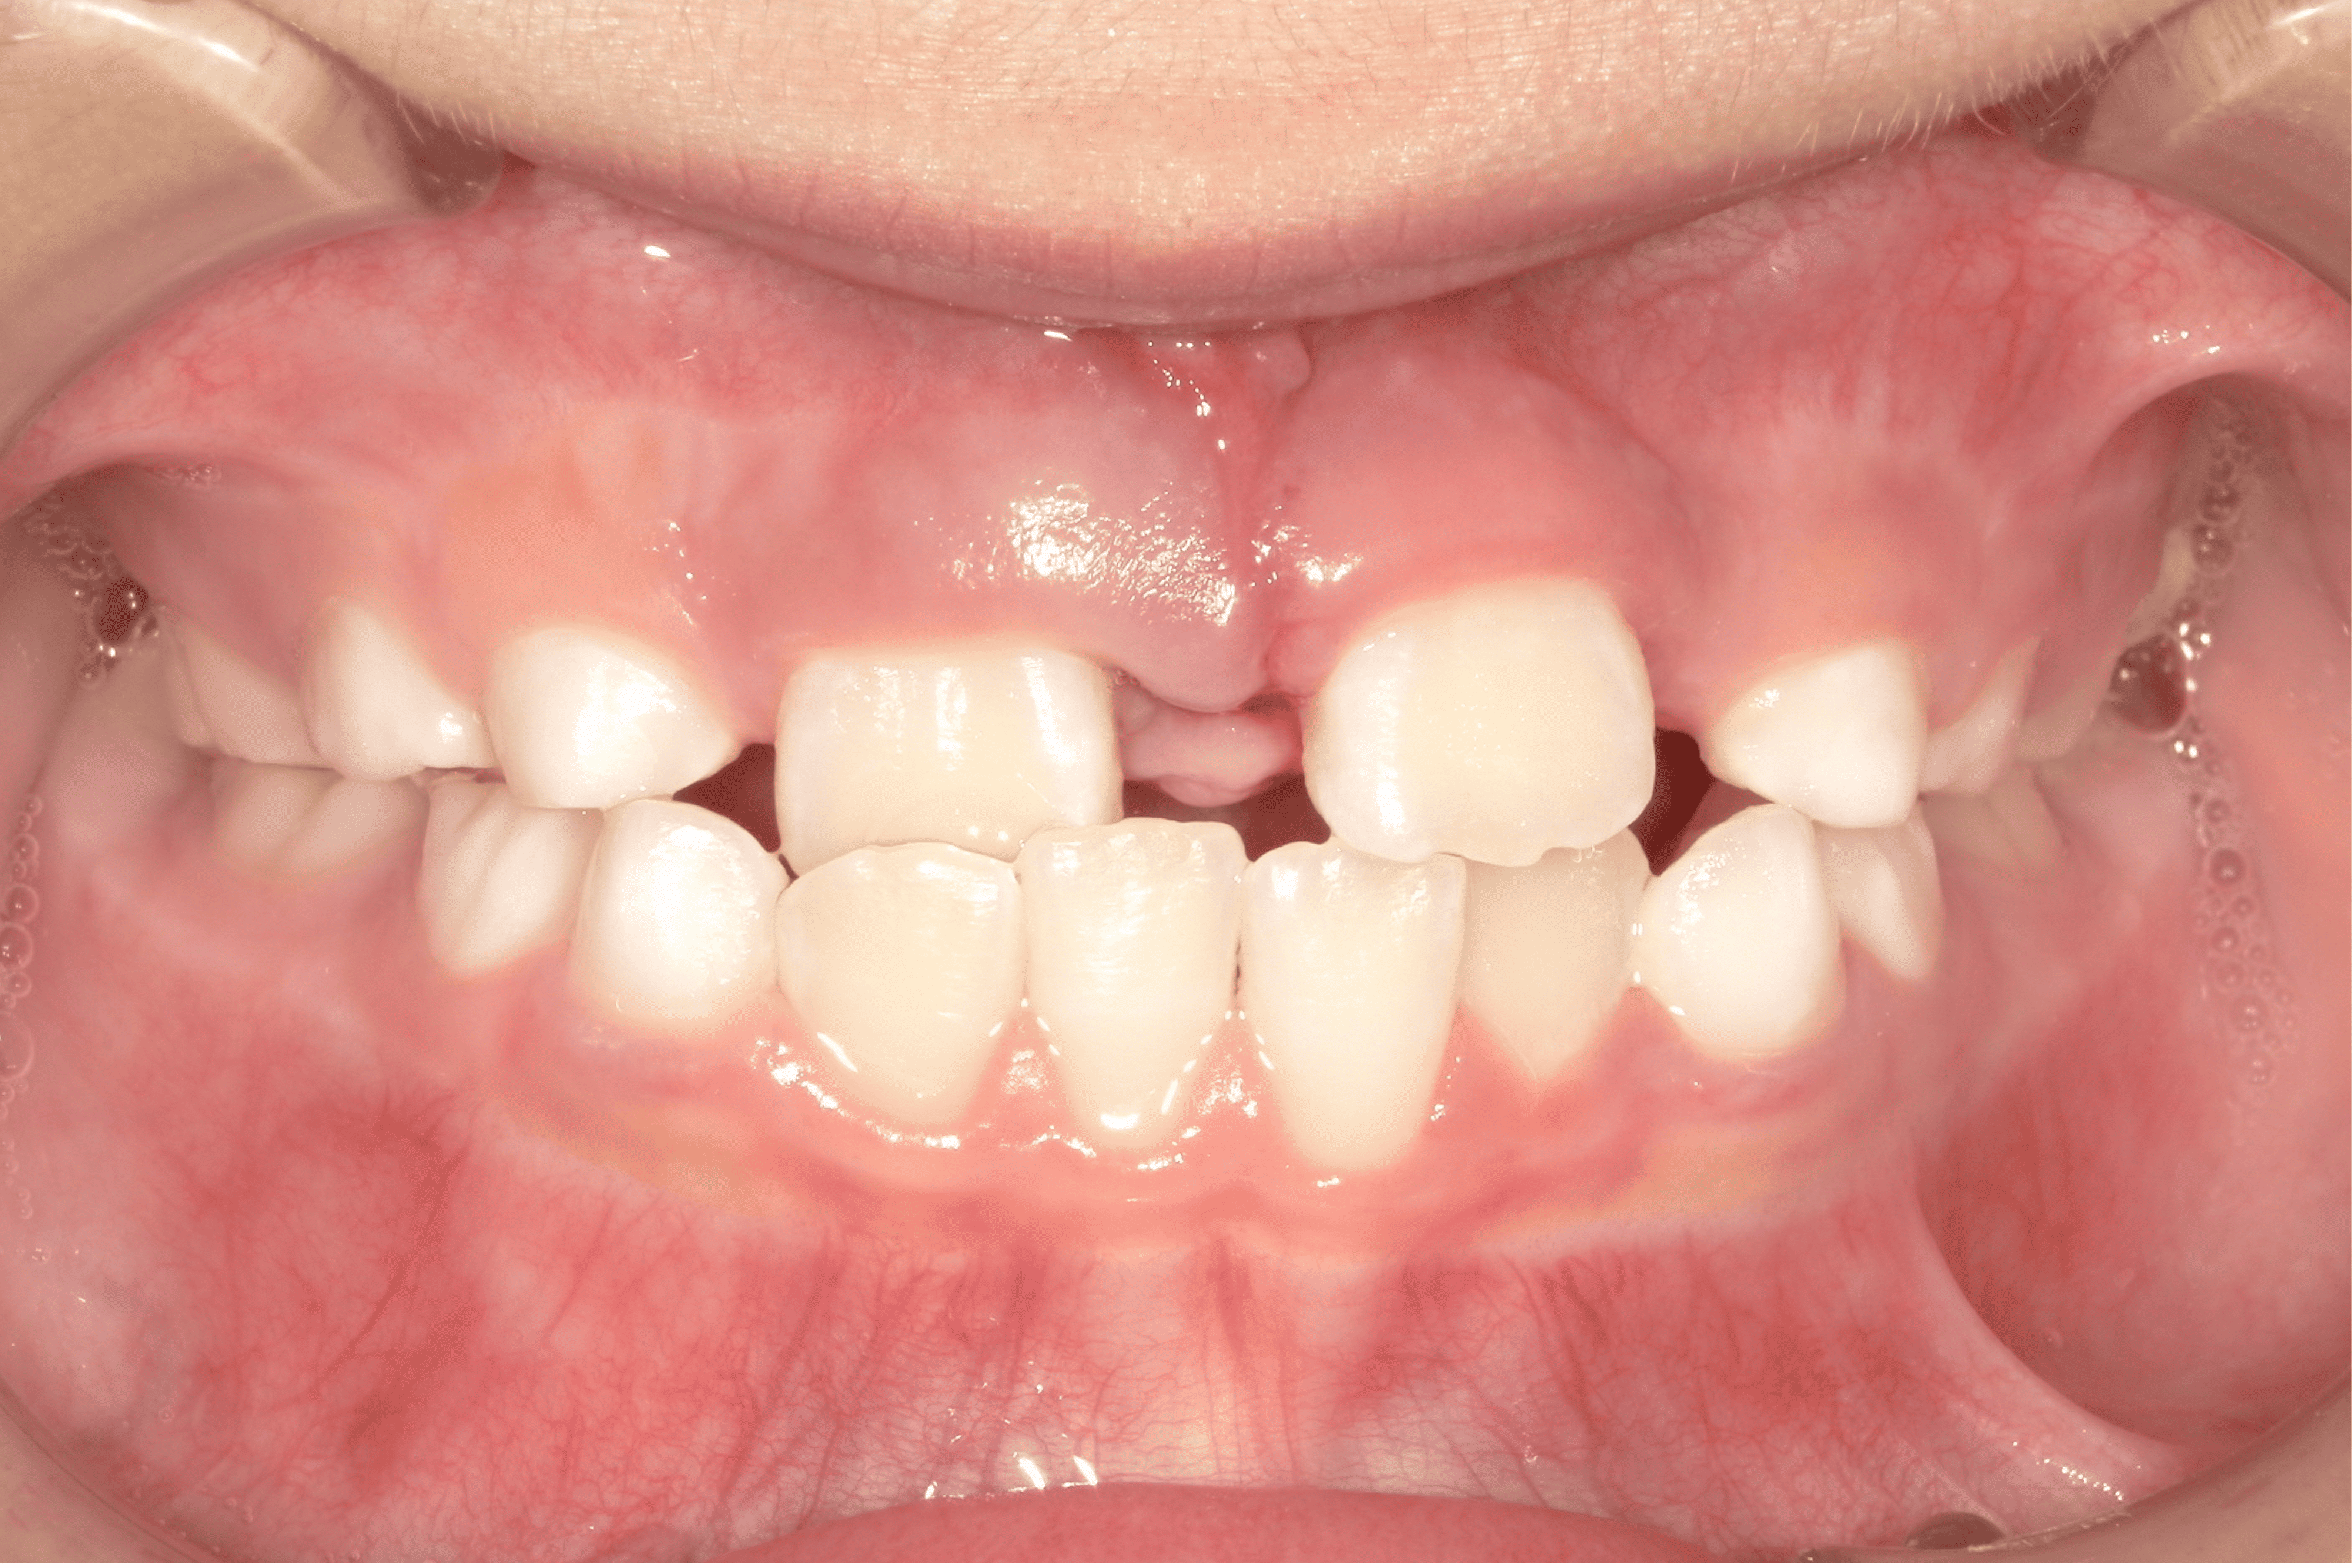

| 年齢・性別 | 7歳1ヶ月の男児 |

|---|---|

| 主訴 | 歯の生えるスペース不足が懸念され、歯列の乱れ(叢生)を整えるために来院された患者様です。 |

| 治療期間・回数 | 1年3ヶ月・11回 |

| 費用 | 420,000円(税別) |